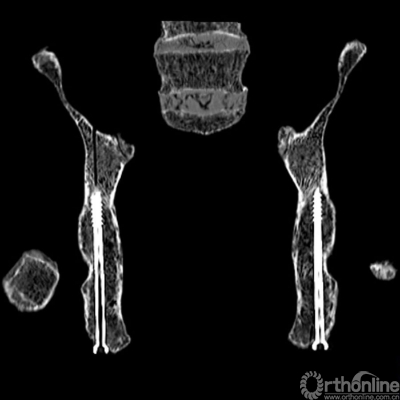

The lag screws were safely inserted into the posterior columns of thepelvic specimens under fluoroscopic control in the iliac oblique view and thetangential views of both the PCPC and medial wall of the acetabulum. During theprocedures, there were no failures in inserting the screws into the properposition. The CT images of the specimens confirmed that the full pathways oflag screws were all in the osseouscorridor of the posterior column. The shortest distance between the posteriorcortex and lag screw was at the level of the greater and lesser sciaticnotches, which was demonstrated on the oblique coronal reconstructed CT images(Figure 6). On the tangential viewsof the PCPC, the greater and lesser sciatic notches also seems closest to thelag screw, which was apparent in the oblique coronal CT images (Figure 4).

Figure 6 The oblique coronalreconstructed CT images shows that the full length of the lag screw is in the boneof the posterior column, and the shortest distance between the posterior cortexand lag screw was at the levels of greater and lesser sciatic notches.